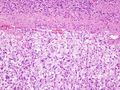

![]() صورة مِجهرية عالية التكبير لورم القواتم بصبغة الهيماتوكسيلين والإيوسين. |

- ترسُّبات من الأميلويد تُرى مِجهريًا

تتكون الأورام من الخلايا أليفة الكروم والتي تكون كبيرة ومتعددة الأشكال. أقل من 10٪ من هذه الأورام خبيثة. وكما هو الحال مع العديد من أورام الغدد الصماء الأخرى، لا يمكن تحديد ماإذا كان الورم خبيثًا أم لا من المظهر النسيجي. يشير الانتشار للأنسجة المحيطة أو الانبثاث بعيدًا إلى كَوْن المرض خبيثًا.